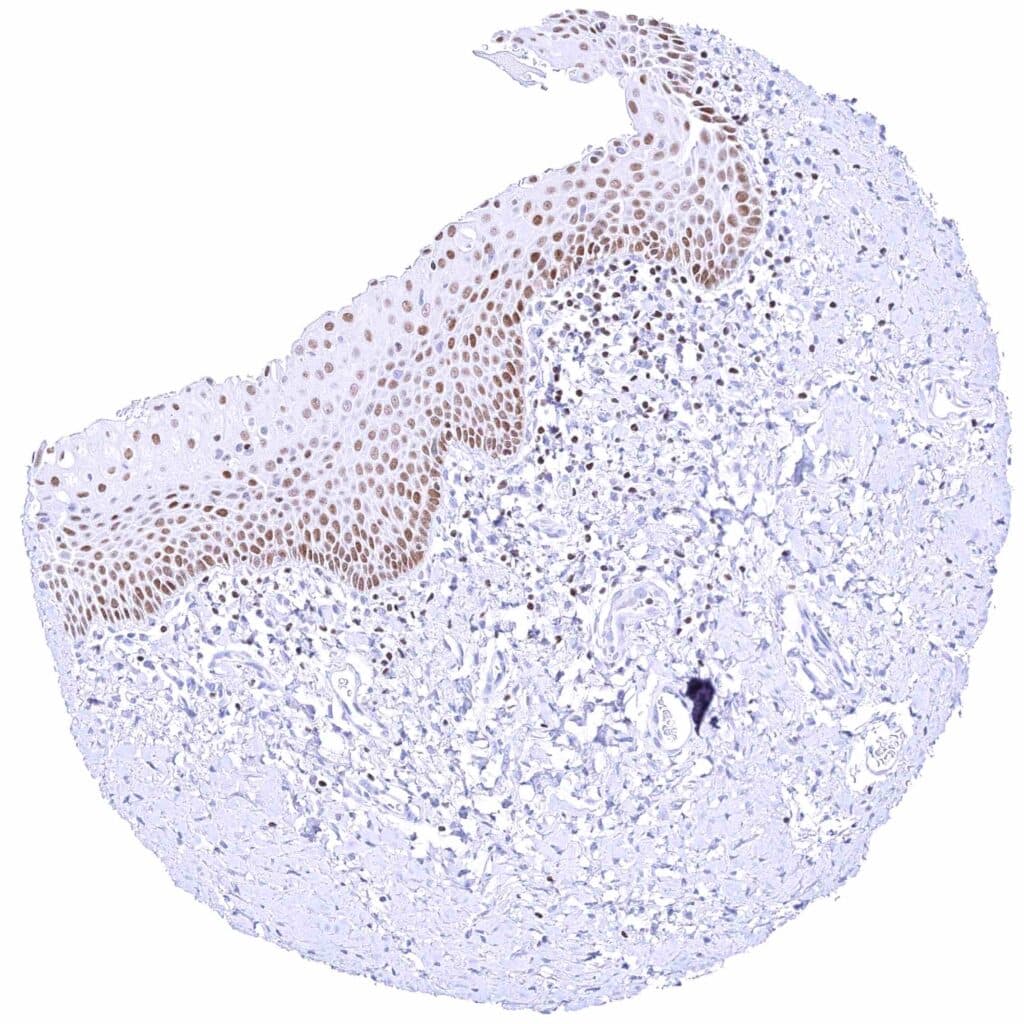

Skin – Strong nuclear GATA3 staining of squamous epithelial cells.

Skin, anal canal – Weak to moderate nuclear GATA3 staining of squamous epithelial cells. The staining predominates in the lower half of the epidermis.